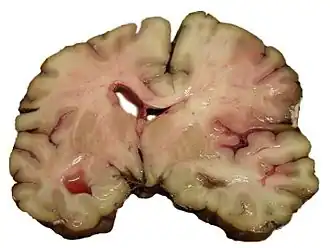

| Срез мозга человека, умершего от инсульта | |